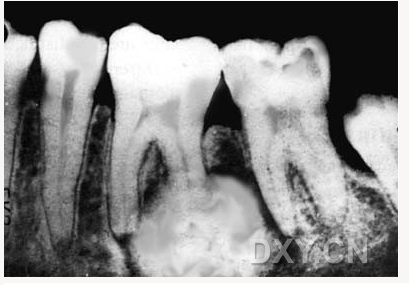

良性成牙骨質(zhì)細胞瘤